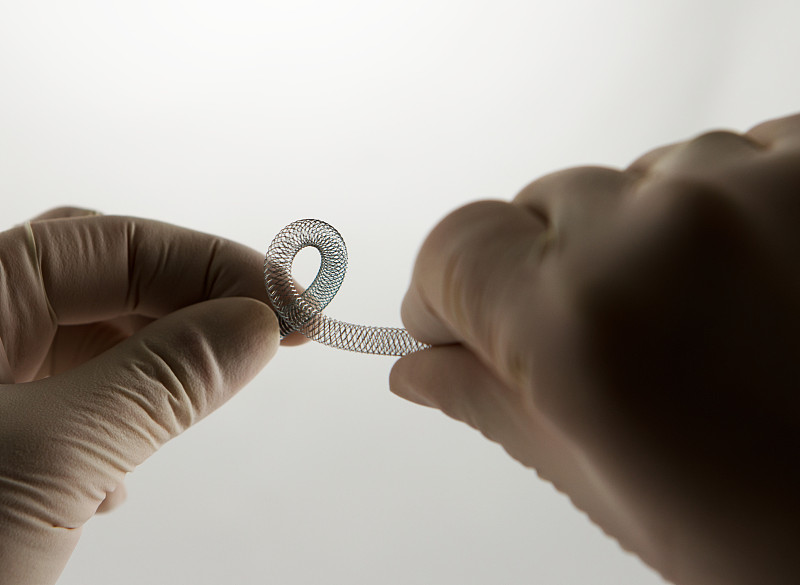

血管内手术支架,扭转详情

JPG